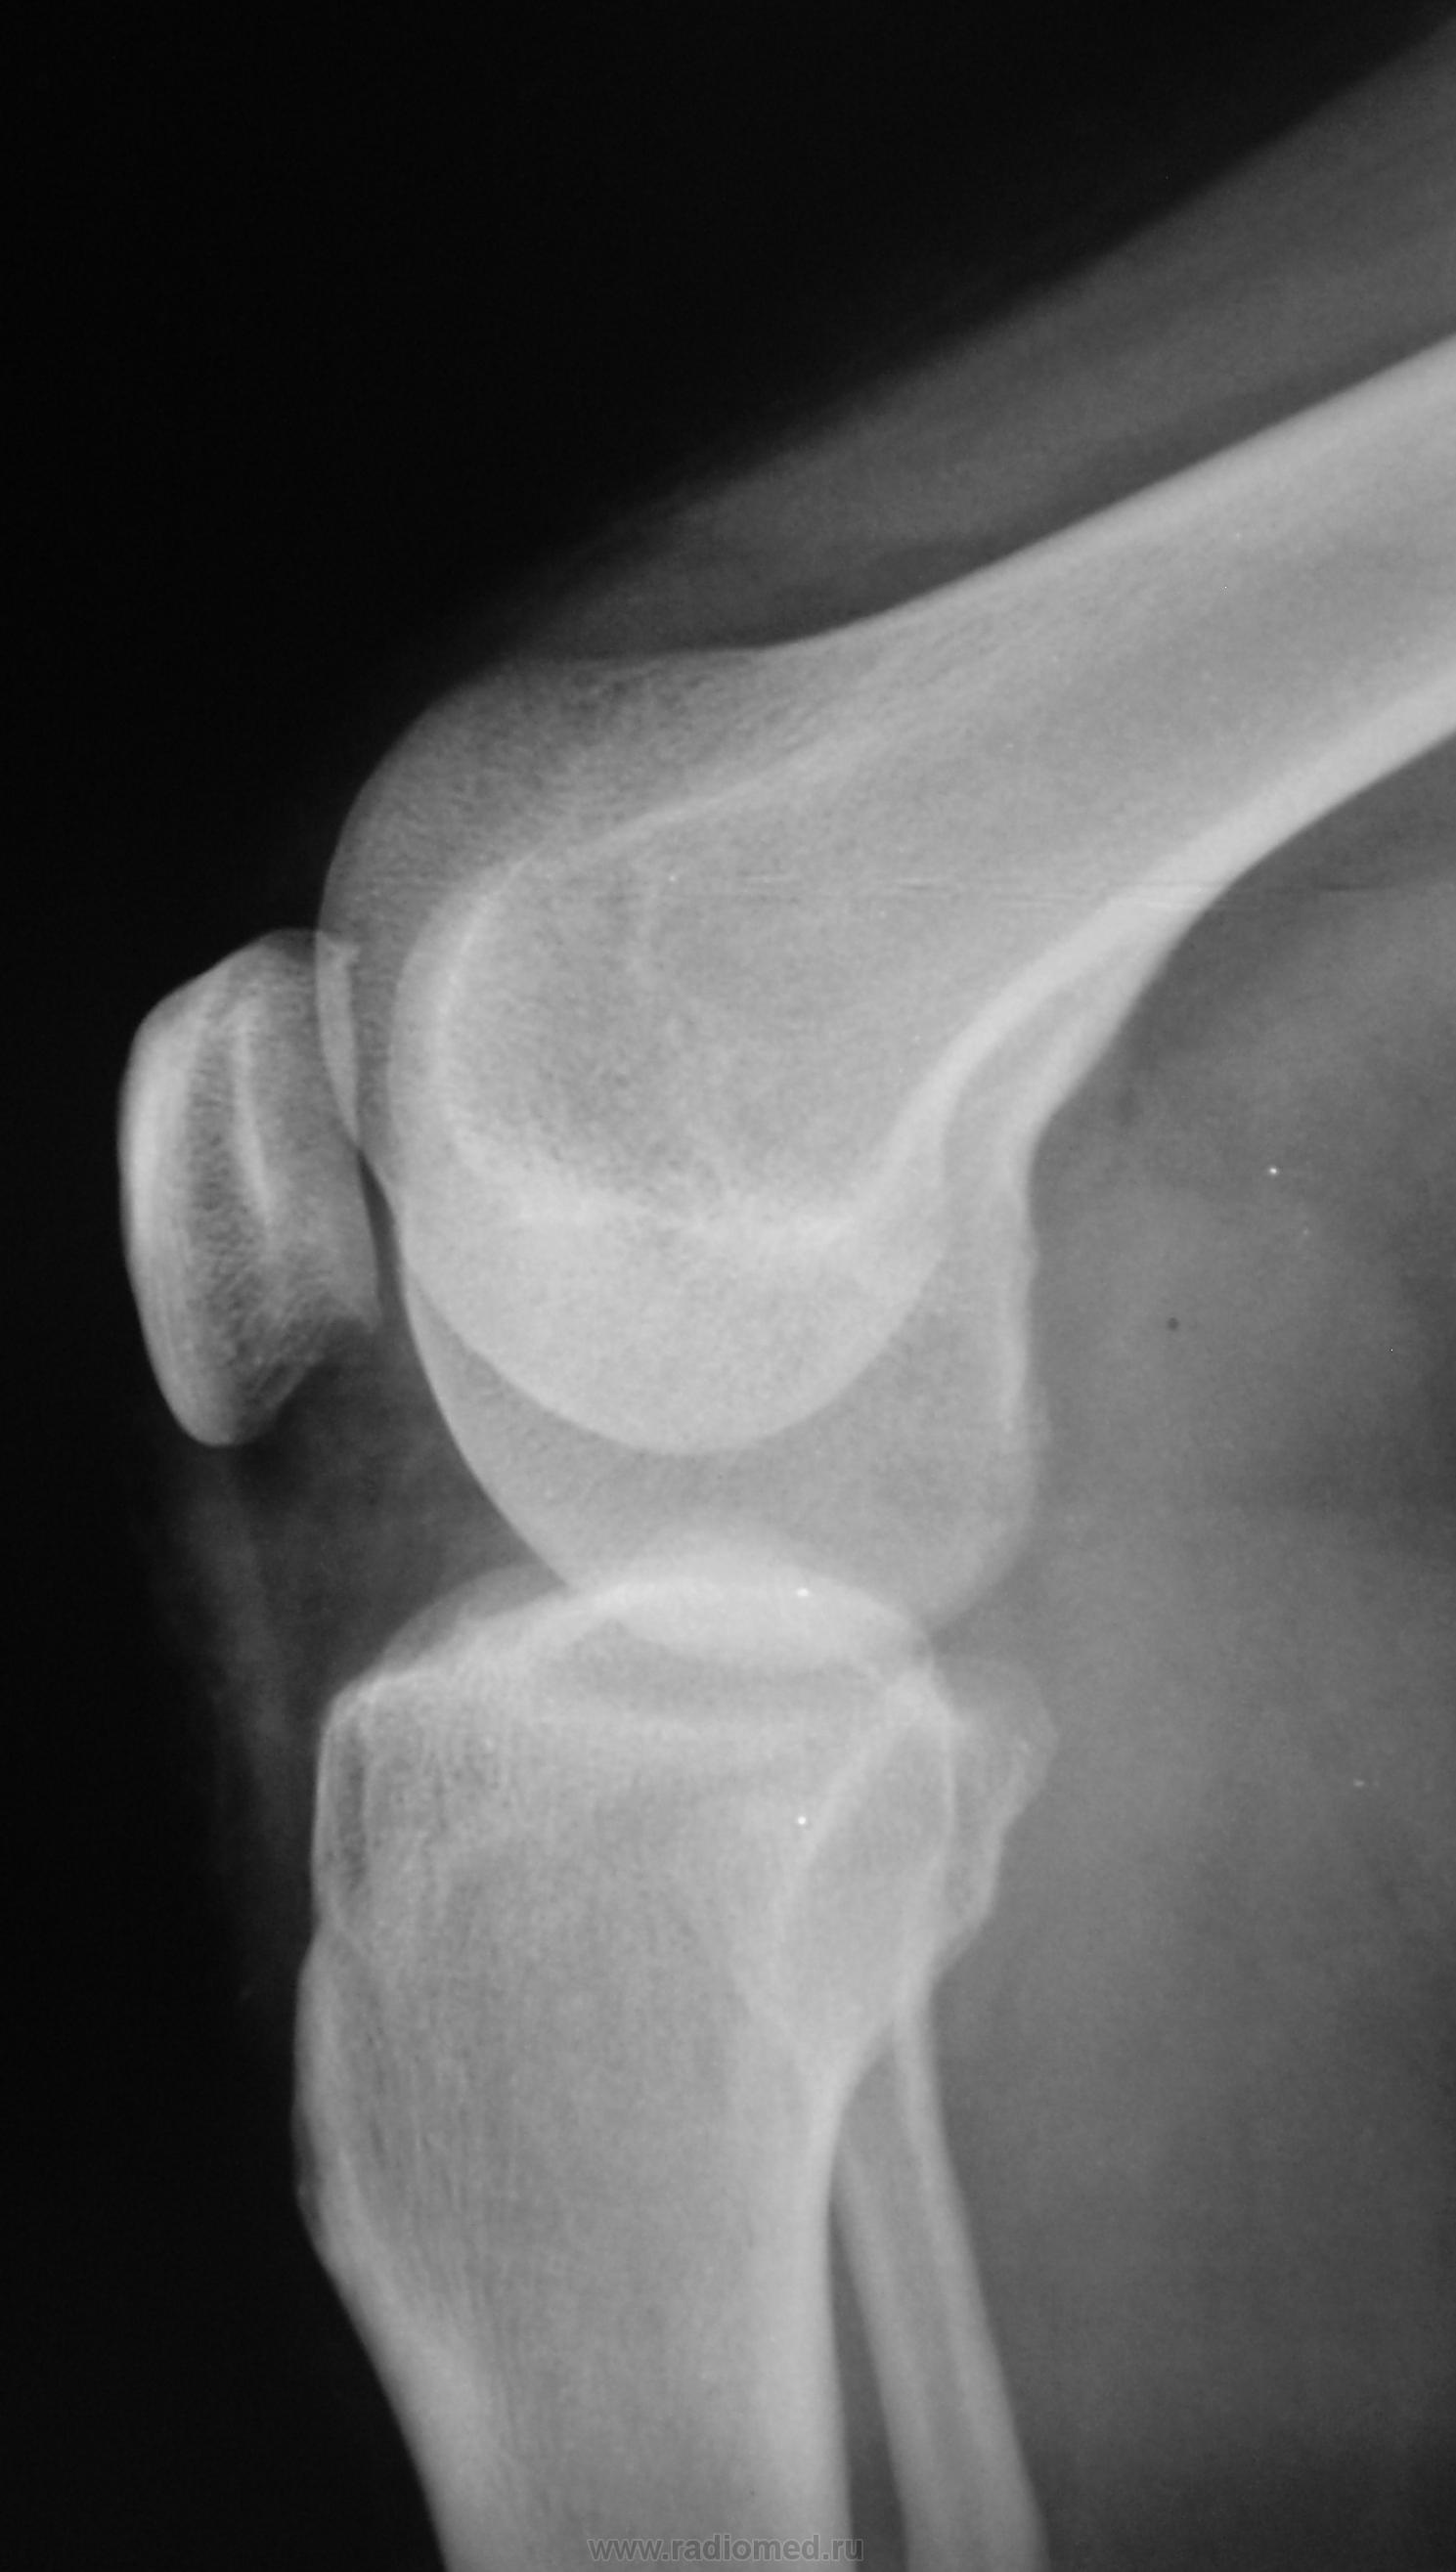

Травма. Пациент направлен на рентгенографию коленного сустава.

Пациент направлен на рентгенографию коленного сустава.

Честно говоря ничего не увидел плохого.

Норма

Определяется уплотнение кортикального слоя суставных поверхностей, заострение межмыщелковых возвышении, слабовыраженная краевая  костная деформация - по совокупности   тянет на ДОА I ст. Ну, а то, что на прицельной то это - игра теней - мое мнение.

Действительно, норма. Такие же суставы в количестве 2 сегодня были и у нас.

Прицельных снимков не делали, это обычных два снимка на цифре.

ДФА 1

артроз пателло-феморального суставчика и лигаментоз крестовидных связок.